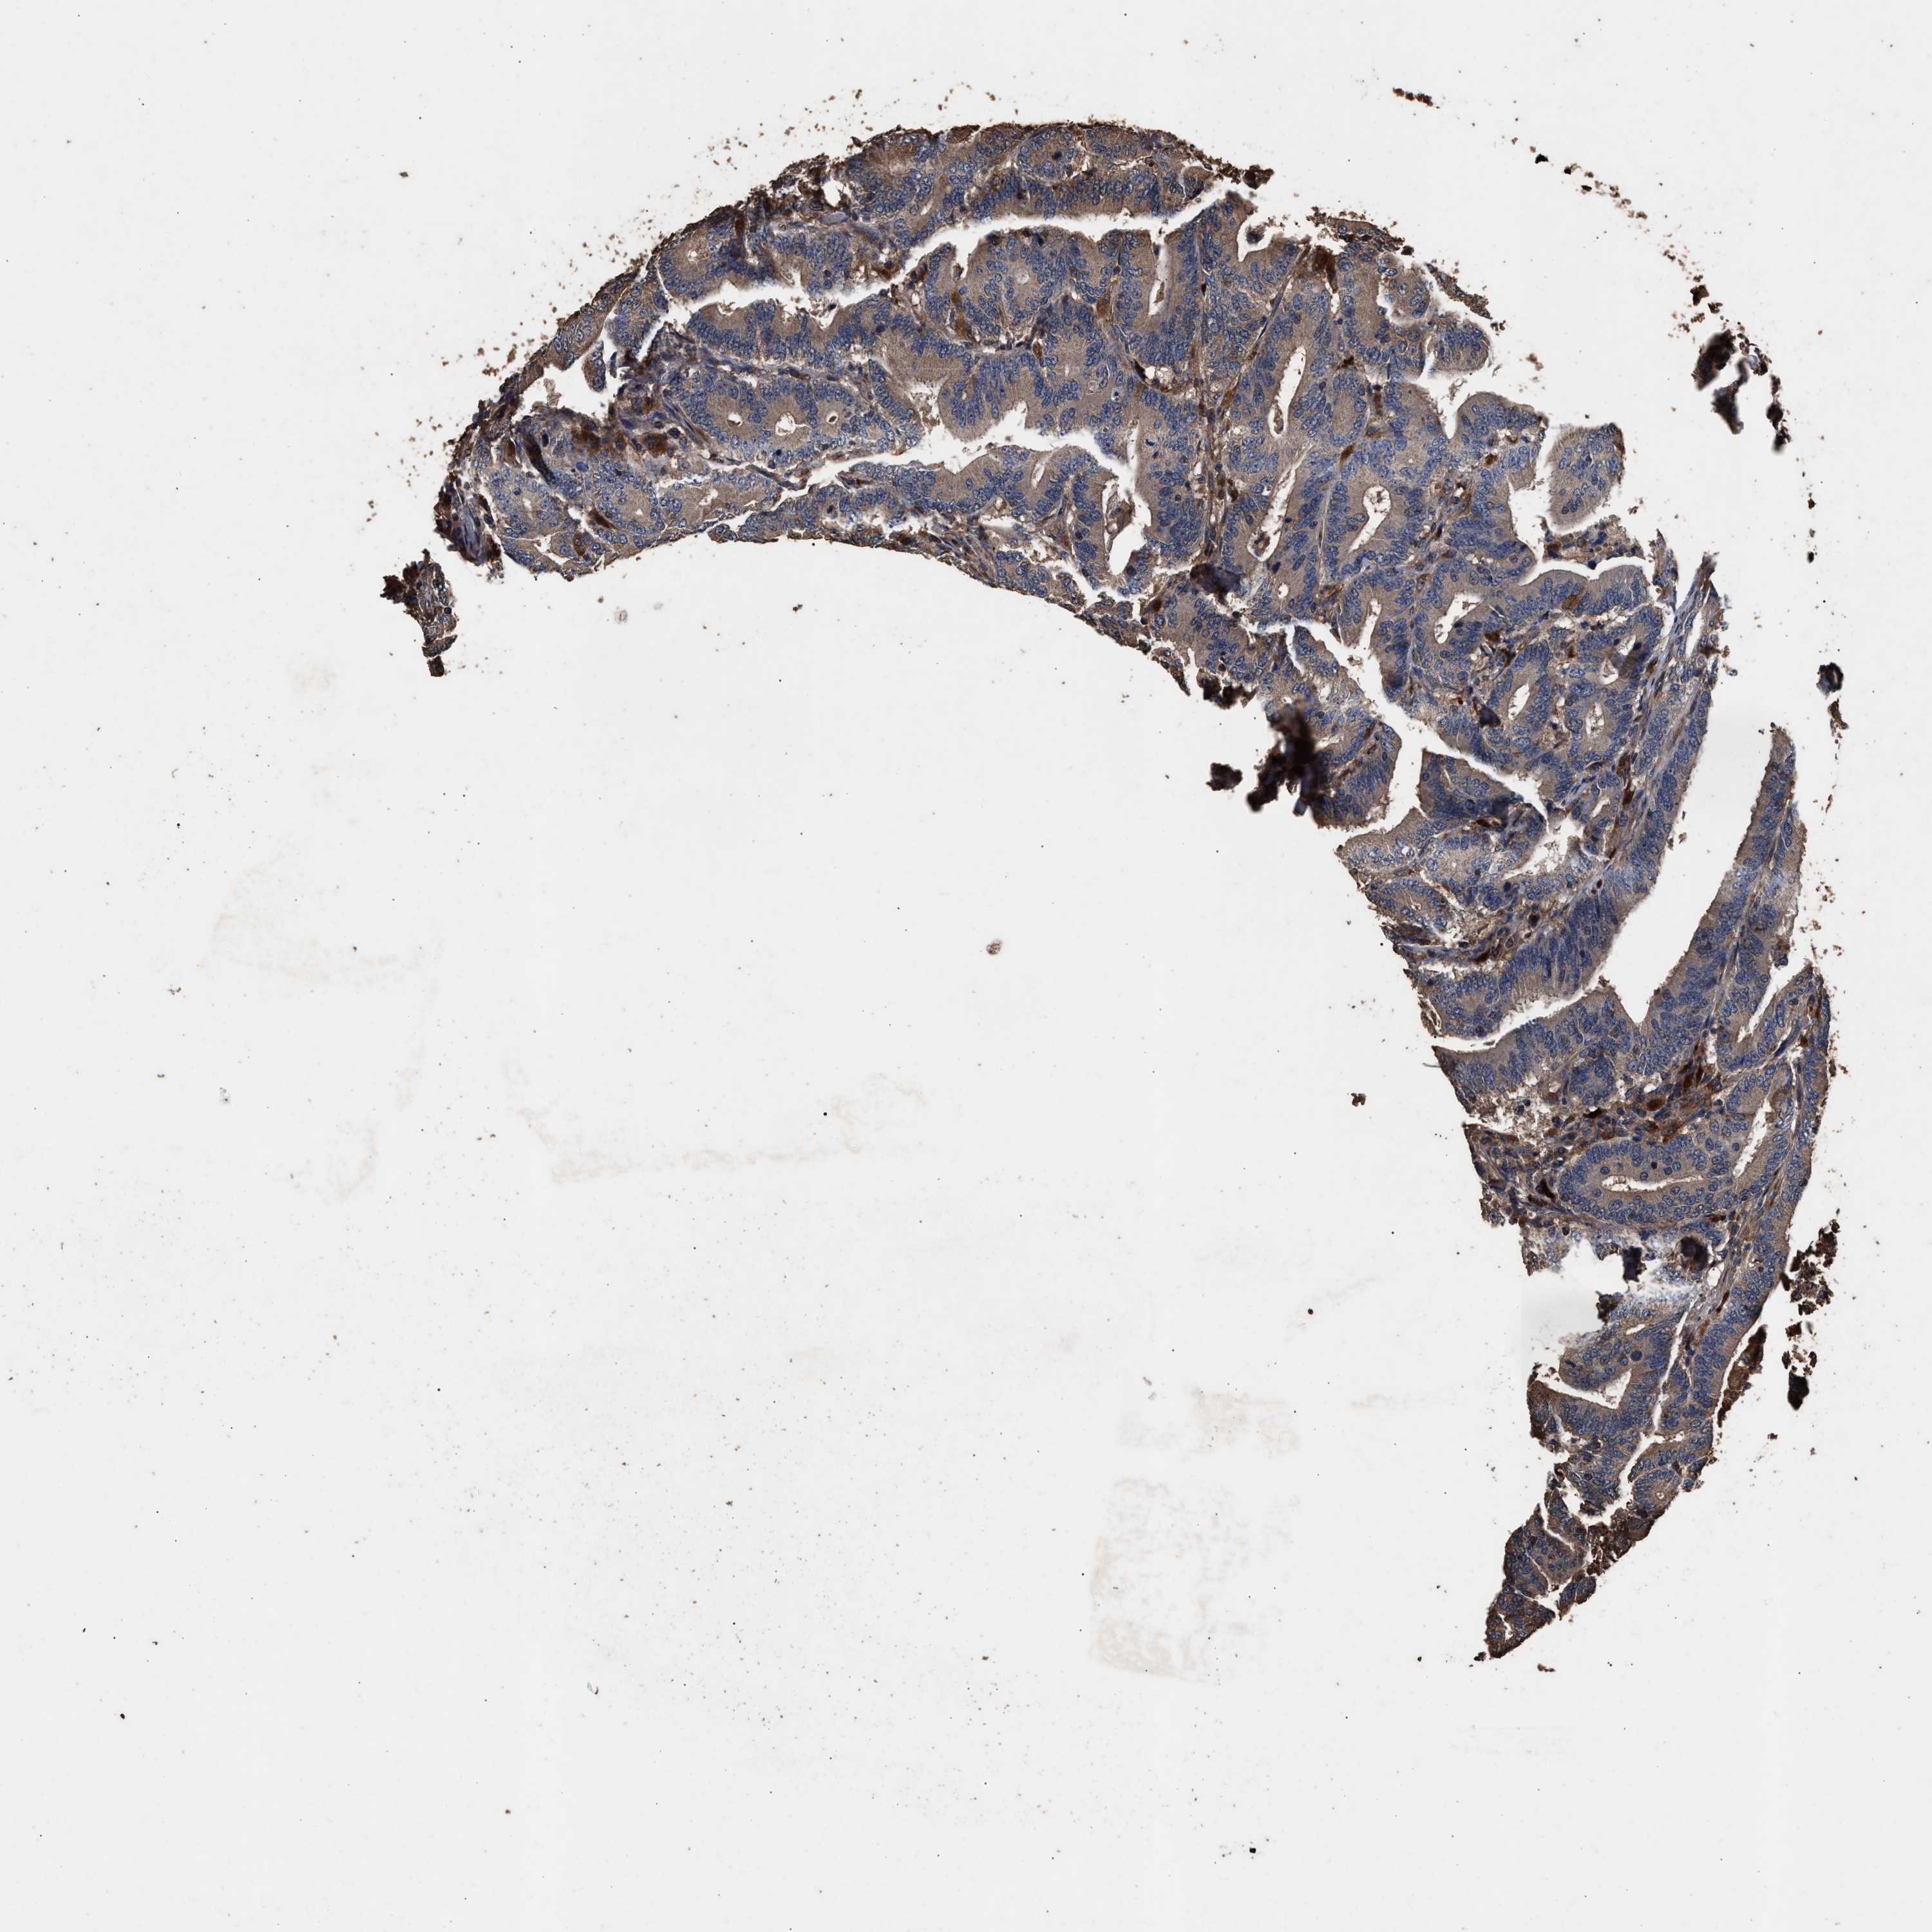

CANCER COLORECTAL CANCER Show tissue menu

Colorectal cancer

Human cancer

Colon adenocarcinoma